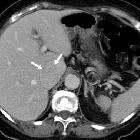

Isolated

intracaval recurrence of resected renal carcinoma. Follow-up contrast-enhanced CT after sunitinib therapy showed dramatic size decrease of tumor thrombosis (a, b) at six months (arrows) and only a small filling defect (c, d) at three years (arrows).

intracaval recurrence of resected renal carcinoma. Follow-up contrast-enhanced CT after sunitinib therapy showed dramatic size decrease of tumor thrombosis (a,b ) at six months (arrows) and only a small filling defect (c, d) at three years (arrows).